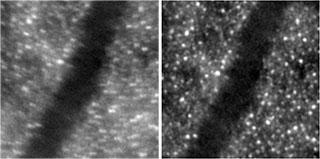

Image de rétine à haute résolution avant (gauche) et après (droite) traitement temps-rapide - système RTX1 d'Imagine Eyes

Image obtenue sur la caméra d’imagerie rétinienne à optique adaptative rtx1 d’Imagine Eyes, intégrant un traitement d'images temps-rapide développé dans l’équipe [Kulcsar2013]. Ce traitement sélectionne les meilleures images dans une séquence de 40 images et les recale de façon fine et robuste.

Nos contributions concernent ici le traitement temps-rapide de la pile de 40 images obtenue lors d’un examen de 4 secondes (10 Hz) par la caméra rtx1 d’Imagine Eyes. Le rtx1 intègre un système d’OA pour compenser les aberrations induites par le cristallin, l’humeur vitreuse, le film lacrymal… L’algorithme intégré dans le rtx1 [Kulcsar2013] permet de sélectionner les meilleures images de la série et de les recaler tout d'abord de façon rigide et robuste. Les mouvements fins de rotation, translation et le grandissement, dus au mouvement de l'œil et de la tête, sont estimés grâce à un modèle géométrique de déformation (affinité). Une version plus performante, mieux adaptée au cas de l'imagerie des vaisseaux de la rétine et basée sur l’estimation du flot optique, a également été proposée [Kulcsar2014].